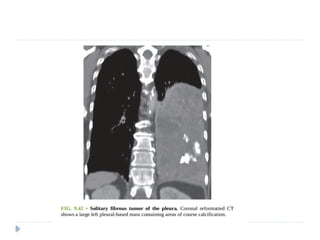

SOLITARY FIBROUS TUMOR OF PLEURA (SFTP)

 Also known as localized fibrous tumor or localized pleural

mesothelioma.

 45- 60 yrs

 Most of the tumors are benign; 20 % cases – malignant.

 Arises from visceral pleural in 80 %

 ON IMAGING :

 Soft tissue pleural-based neoplasm

 Areas of necrosis, hemorrhage, and cystic changes.

 Calcification may be seen in up to 26% of cases.

 Heterogeneous enhancement is seen post-contrast.

 On magnetic resonance imaging (MRI), hypointense solid mass is

seen on T1- and T2-weighted images. Necrosis and cystic

degeneration changes show high T2 signal intensity.

Benign pleural fibroma.

Enhanced CT reveals a soft tissue

intrafissural mass with coarse

calcifications, pathologically consistent

with a benign pleural fibroma.